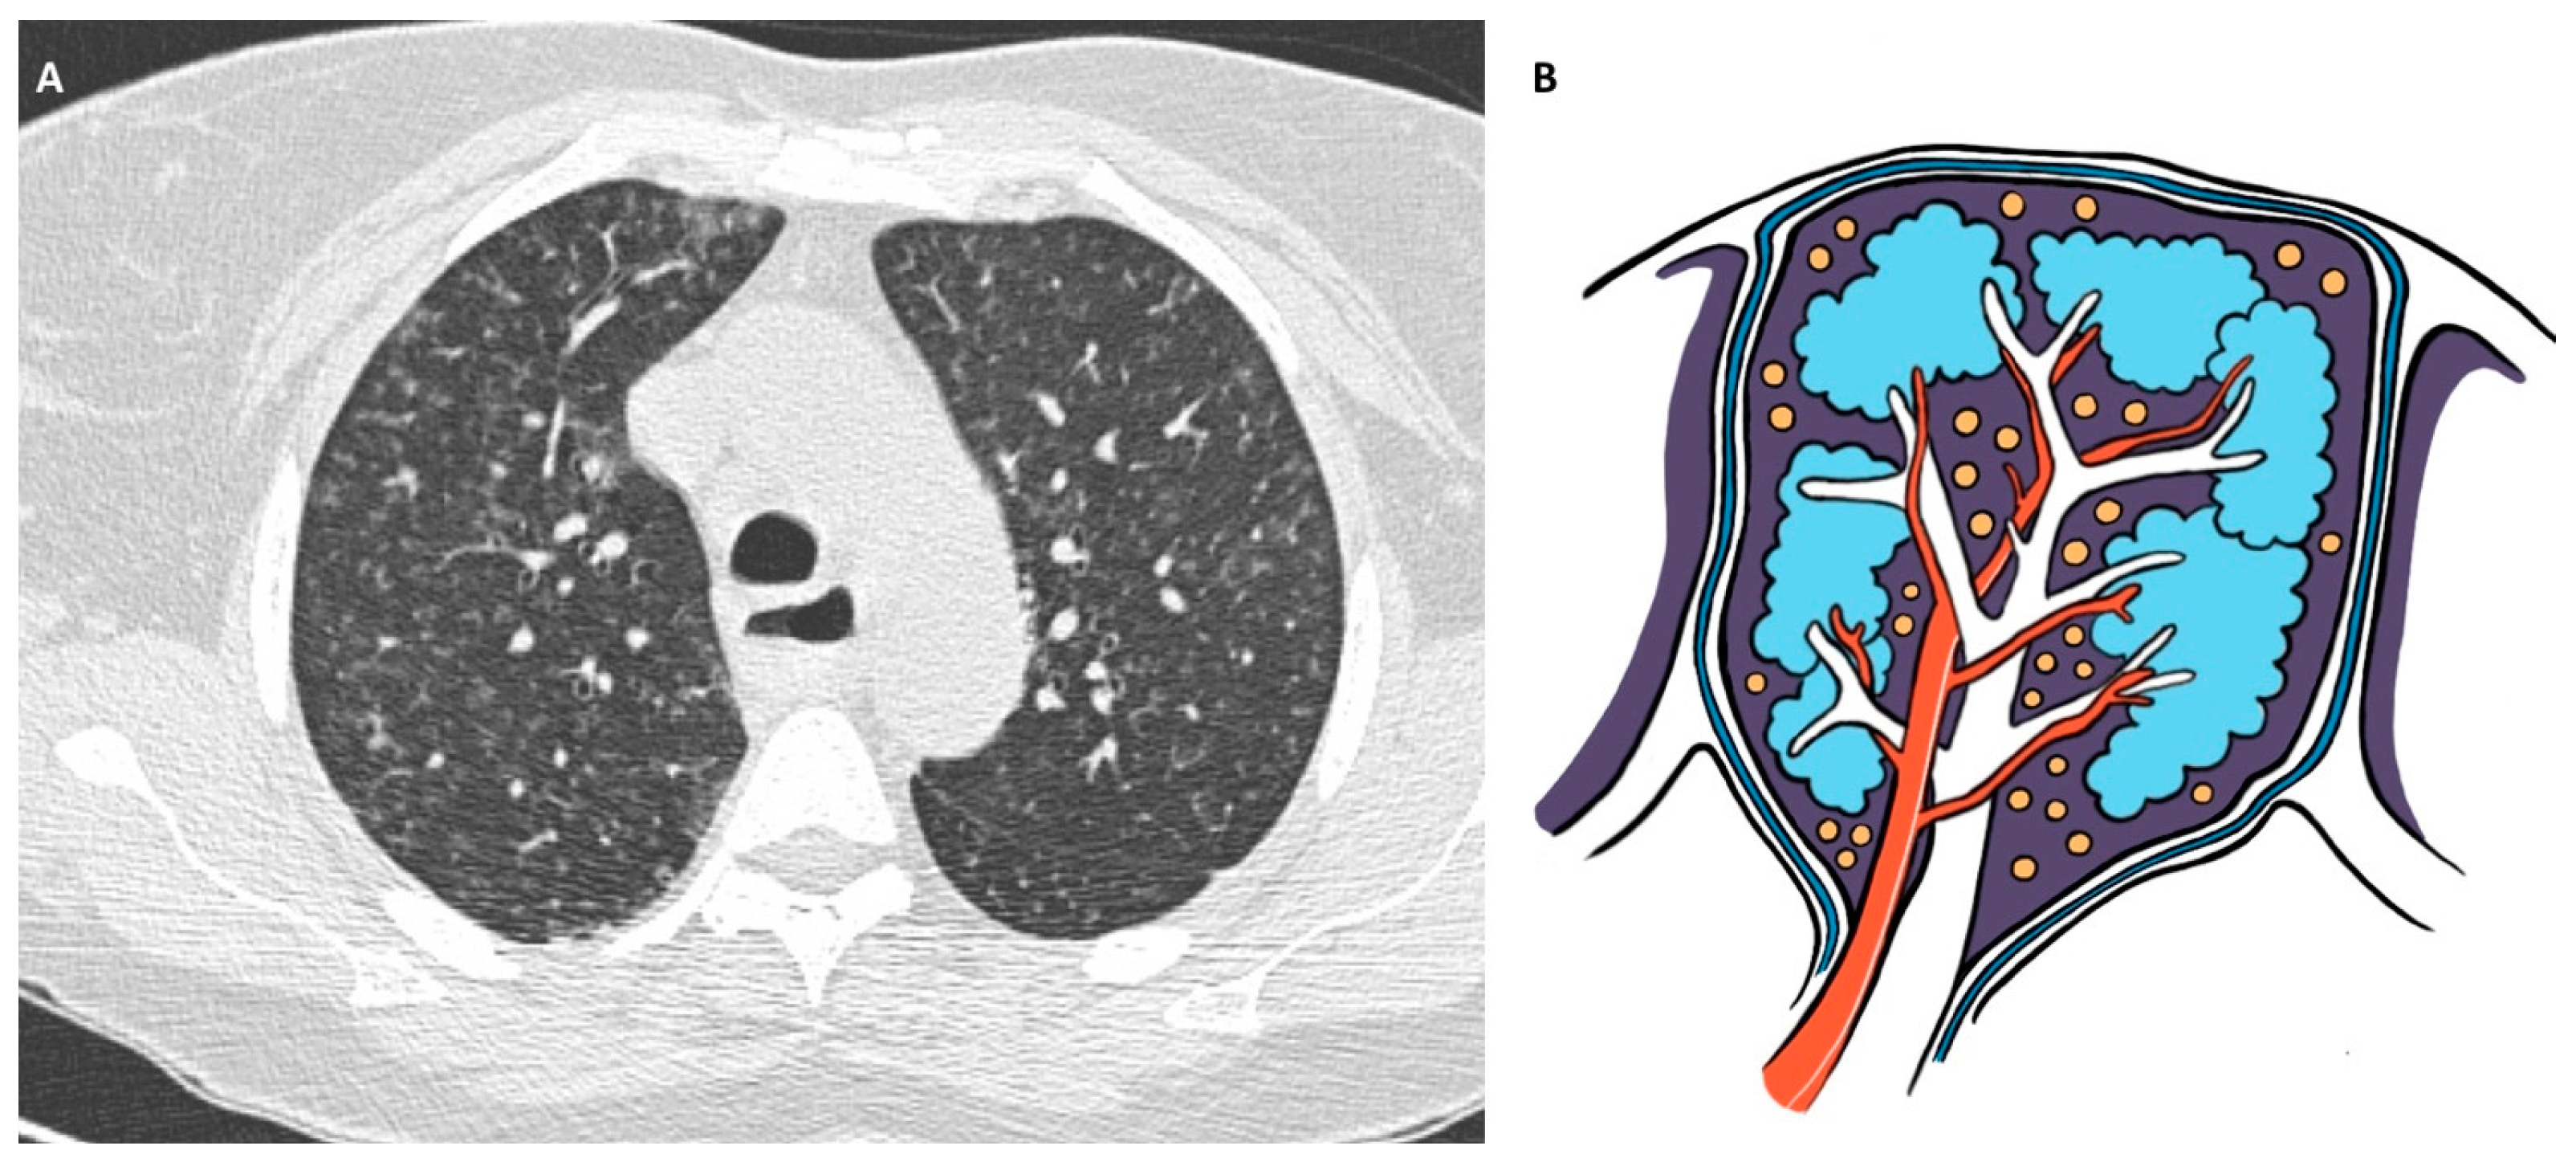

5.1. Hypersensitivity Pneumonitis

5.1.4. Diagnosis